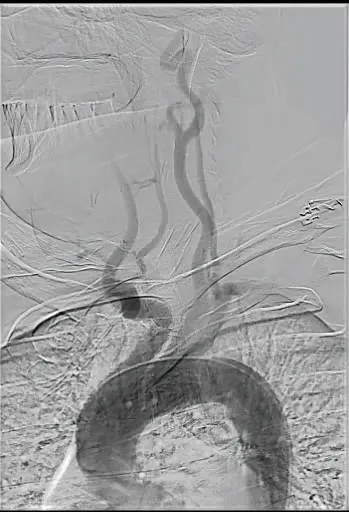

After ultrasound-guided transfemoral access, the patient was systemically heparinized. An aortic arch angiogram demonstrated a bovine, type II arch configuration. The CCA was selectively cannulated using a Van Schie 4 catheter (Cook Medical) and Glidewire® (Terumo Interventional Systems). Angiography confirmed a critical focal stenosis at the distal anastomosis of the bypass graft (Figure 2A). For enhanced stability, a 7-F Destination™ sheath (Terumo Interventional Systems) was advanced into the proximal CCA. A distal filter wire was then carefully navigated across the lesion and deployed in the distal ICA. A 10- X 20-mm Roadsaver™ dual-layer micromesh carotid stent (Terumo Interventional Systems) was advanced and deployed across the anastomotic stenosis. Postdilation was performed using a 5- X 40-mm angioplasty balloon to optimize luminal expansion and stent apposition. Completion angiography demonstrated an excellent result, with no residual stenosis, preserved distal flow, and no angiographic evidence of embolization (Figure 2B). The filter was retrieved and was free of visible debris, and the patient experienced no periprocedural neurologic events.

Figure 2. Selective angiography of the left carotid artery showing a focal severe luminal stenosis > 80% (A). Completion angiography post Terumo Roadsaver carotid stent demonstrating no residual stenosis (B).